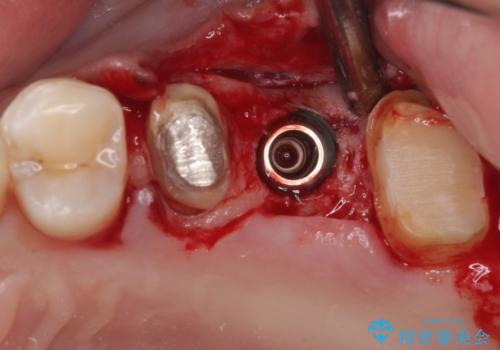

インプラントが必要となった奥歯は、インプラントが埋入できないほど隣の歯の根尖病変が非常に大きかったため、根管治療を行ったうえで半年ほど待ち、骨が再生したことを確認してからインプラントを埋入しました。期間は長くかかりましたが、大変良い仕上がりとなりました。